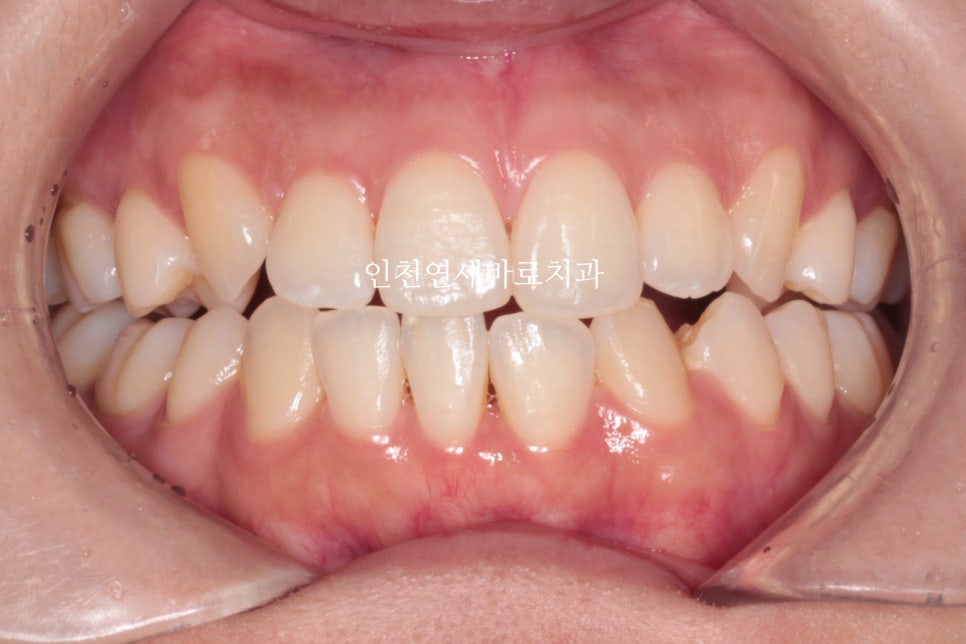

지난 주 마무리된 모습

결손치아가 있지만 교합은 문제없게 마무리

그리고 중요한 앞모습

과정이야 힘들고 오래걸리고 장치도 교체하고 어려웠지만

목표한바는 모두 달성한 치료입니다.